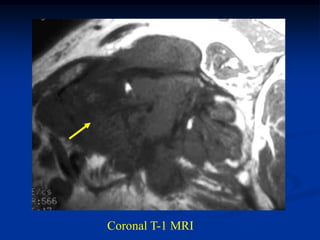

Case #261

62 year female

MFH anterior thigh

AP x-ray

Case #261 62 yearfemale MFH anterior thigh AP x-ray